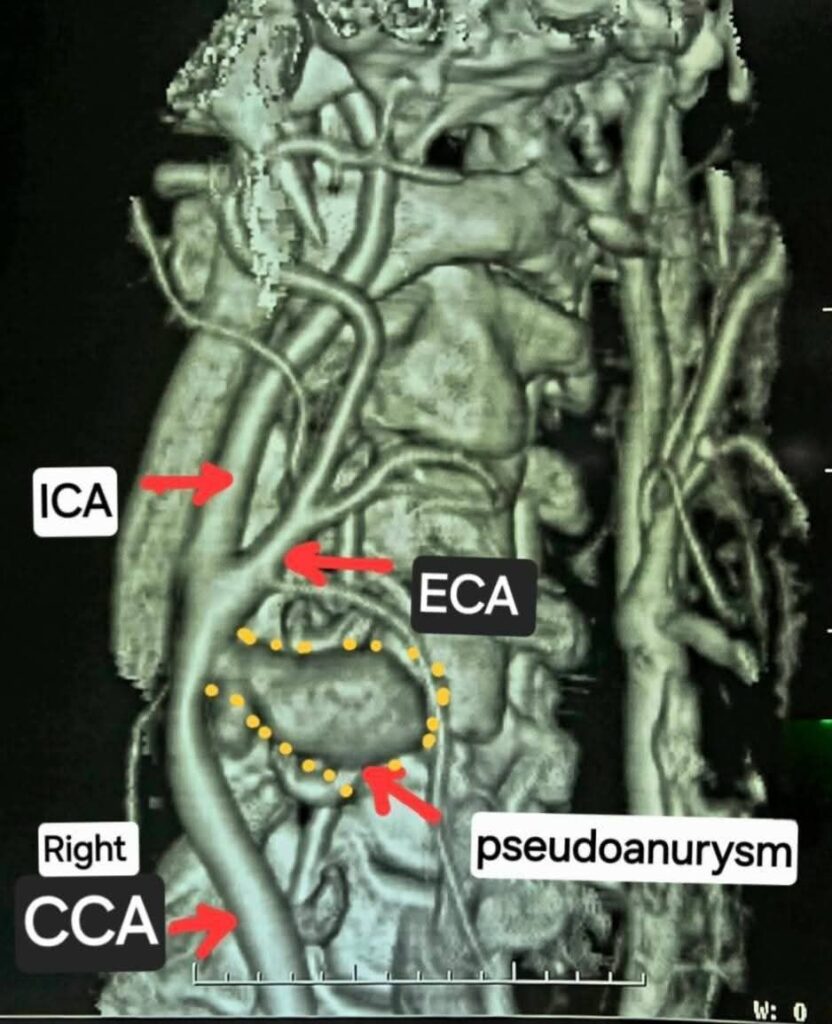

मेकाहारा में की गई सीटी एंजियोग्राफी जांच में चौंकाने वाला खुलासा हुआ। मरीज की दाहिनी कैरोटिड आर्टरी अपने आप फट चुकी थी और उसके आसपास खून जमकर एक खतरनाक गुब्बारे जैसी संरचना बन गई थी, जिसे मेडिकल भाषा में कैरोटिड आर्टरी स्यूडोएन्युरिज्म कहा जाता है। कैरोटिड आर्टरी दिल से सीधे दिमाग तक ऑक्सीजनयुक्त खून पहुंचाने वाली मुख्य नस होती है। इसका फटना सीधे तौर पर जानलेवा स्थिति मानी जाती है, जिससे ब्रेन में ब्लड सप्लाई रुक सकती है, लकवा या ब्रेन डेड होने तक का खतरा रहता है।

डॉक्टरों के अनुसार बिना किसी चोट, संक्रमण या पुरानी बीमारी के अपने आप कैरोटिड आर्टरी का फटना दुनिया भर में बेहद दुर्लभ है। अंतरराष्ट्रीय मेडिकल जर्नल्स में ऐसे केवल 10–12 केस ही दर्ज हैं। यह मरीज पूरी तरह स्वस्थ था, जिससे यह केस और भी चुनौतीपूर्ण हो गया। गर्दन में अत्यधिक खून जमा होने के कारण सर्जरी के दौरान नस को पहचानना तक मुश्किल था।

हार्ट, चेस्ट एवं वैस्कुलर सर्जरी विभाग के प्रमुख डॉ. कृष्णकांत साहू के नेतृत्व में डॉक्टरों की टीम ने कई घंटे तक चली हाई रिस्क सर्जरी को अंजाम दिया। फटी हुई नस को रिपेयर करने के लिए बोवाइन पेरिकार्डियम पैच जैसे विशेष बायोलॉजिकल मटेरियल का इस्तेमाल किया गया। ऑपरेशन के दौरान हर पल गंभीर खतरा बना रहा, क्योंकि जरा सी चूक मरीज को स्थायी लकवे या गंभीर ब्रेन डैमेज की ओर ले जा सकती थी।